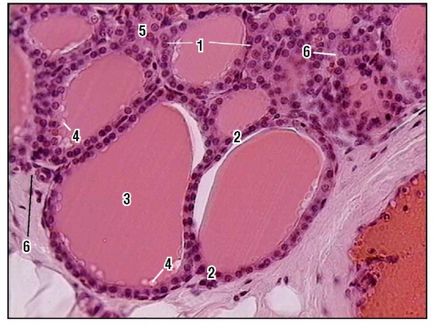

Fig. 169. Fragmentul lobulei glandei tiroide (colorare cu hematoxilină și eozină, creștere mare): 1 - folicul; 2 - celule foliculare (tirocite); 3 - coloid; 4 - vacuole; 5 - epiteliul interfollicular; 6 - capilar